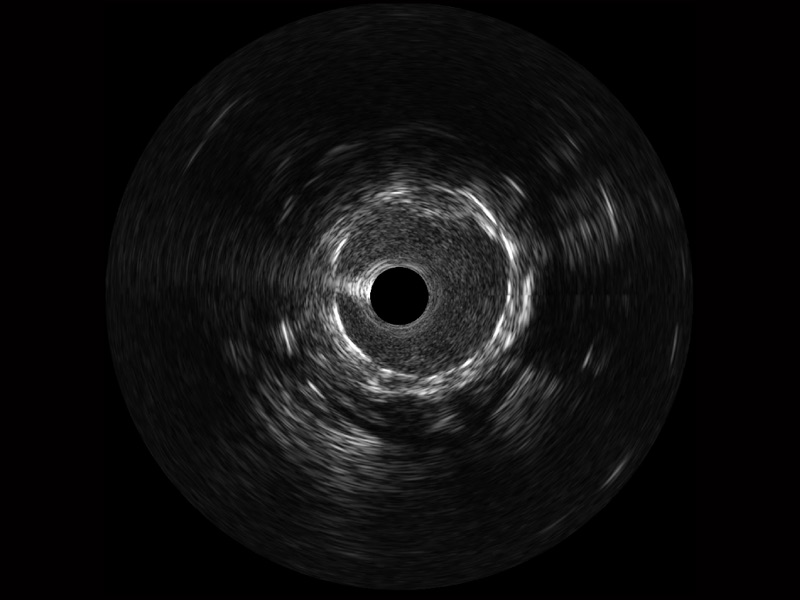

球速体育入口宽频IVUS图像

传统IVUS图像

对比传统IVUS导管成像,球速体育入口宽频IVUS图像的近场支架梁显影更细腻,远场中膜外血管仍清晰可辨,兼顾远中近,兼顾分辨力与穿透深度